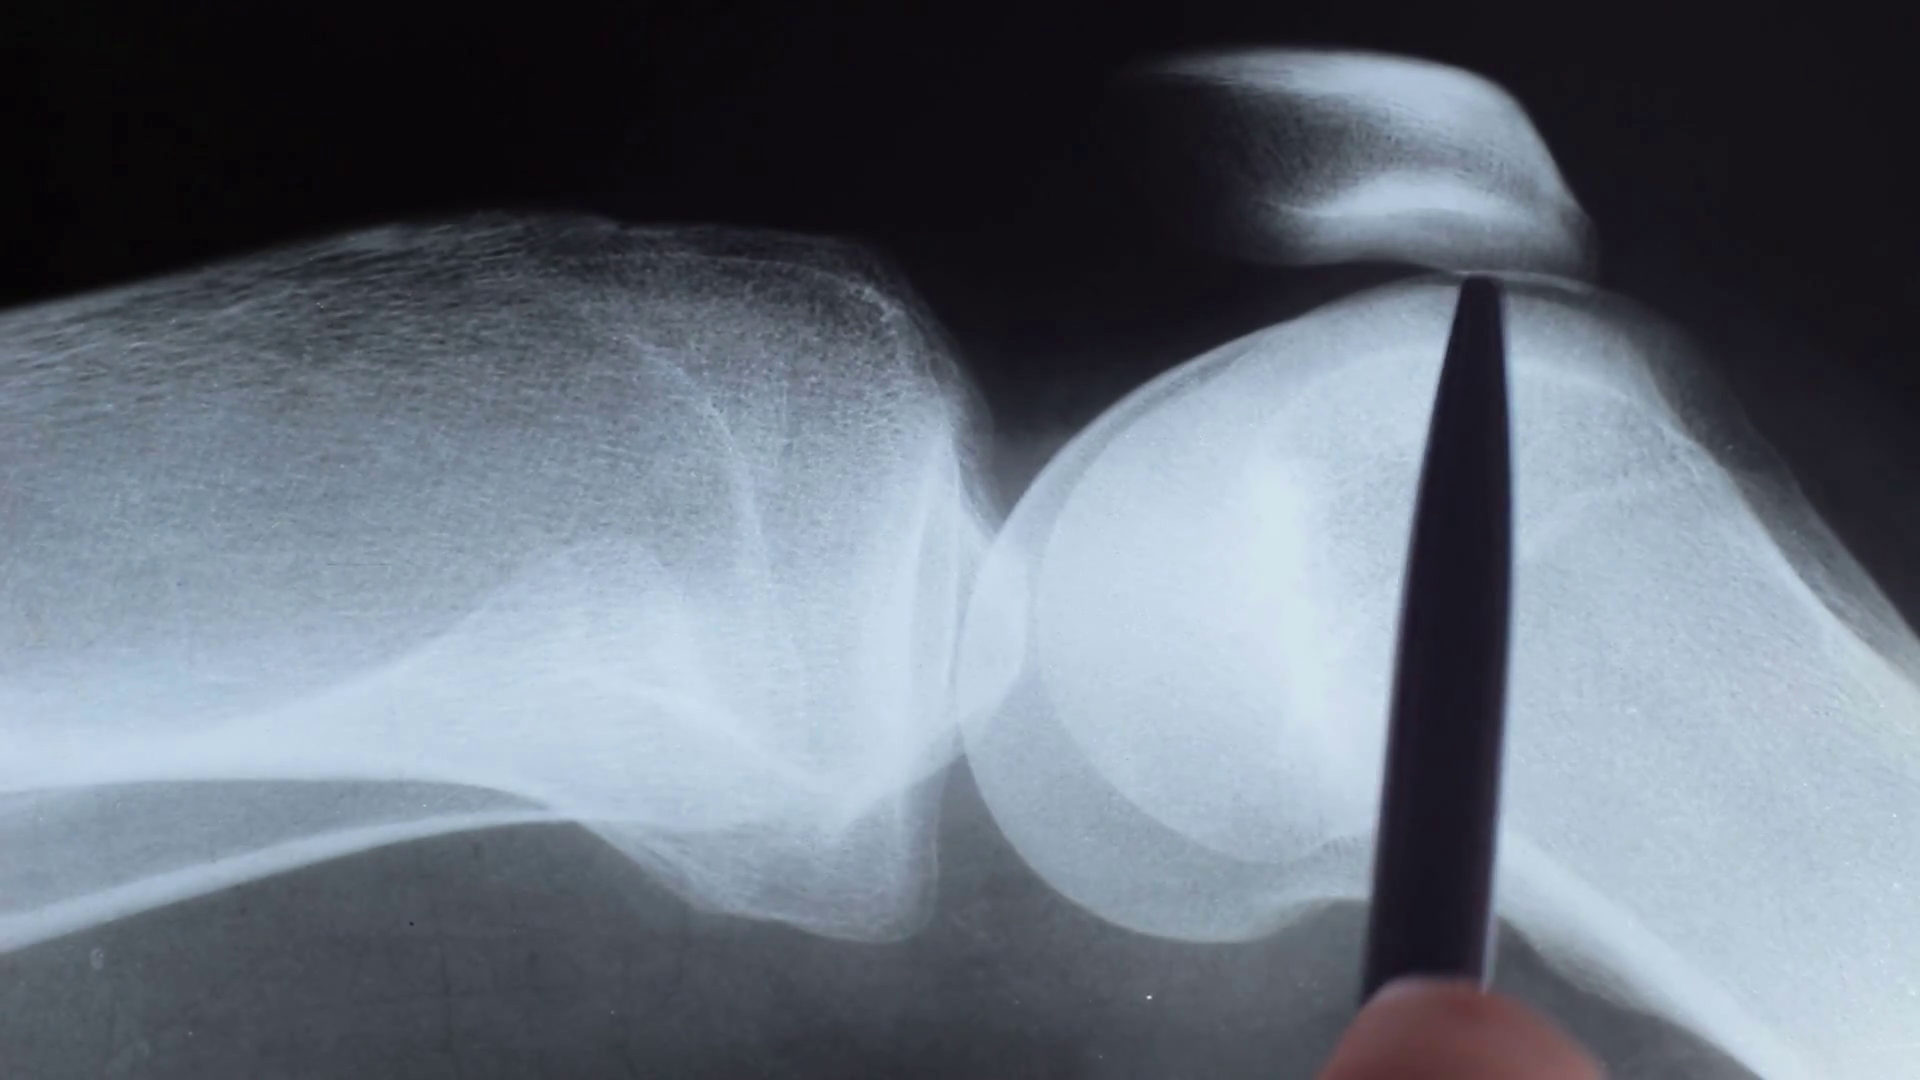

Back Of Knee Pain Diagnosis Chart